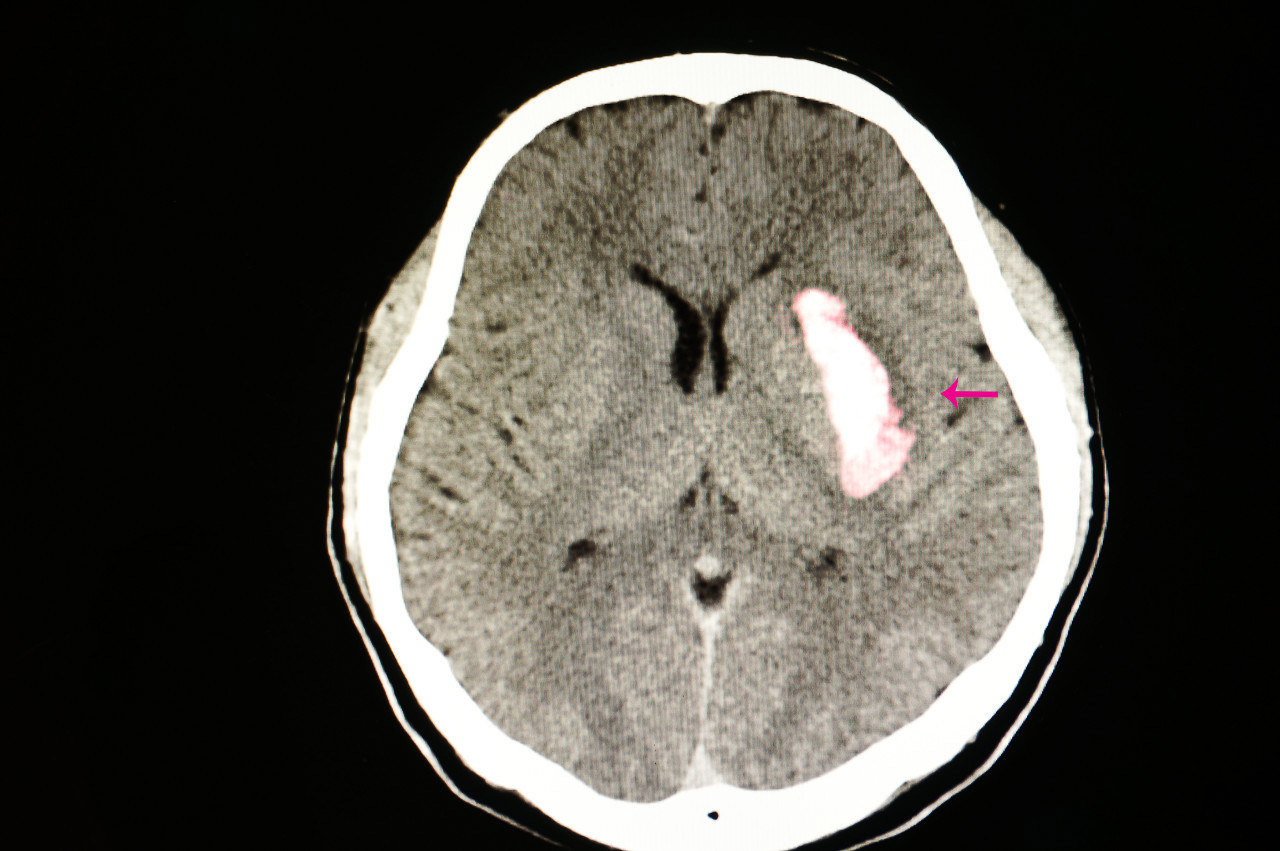

基底节区脑出血严重吗

左侧基底节区脑出血是一种因左侧基底节区血管破裂导致血液在脑实质内积聚的严重疾病症状表现症状与出血量及位置密切相关常见症状包括突发剧烈头痛呕吐一侧肢体无力或麻木,可能伴随面部手臂或腿部瘫痪言语不清或理解困难失语意识模糊...